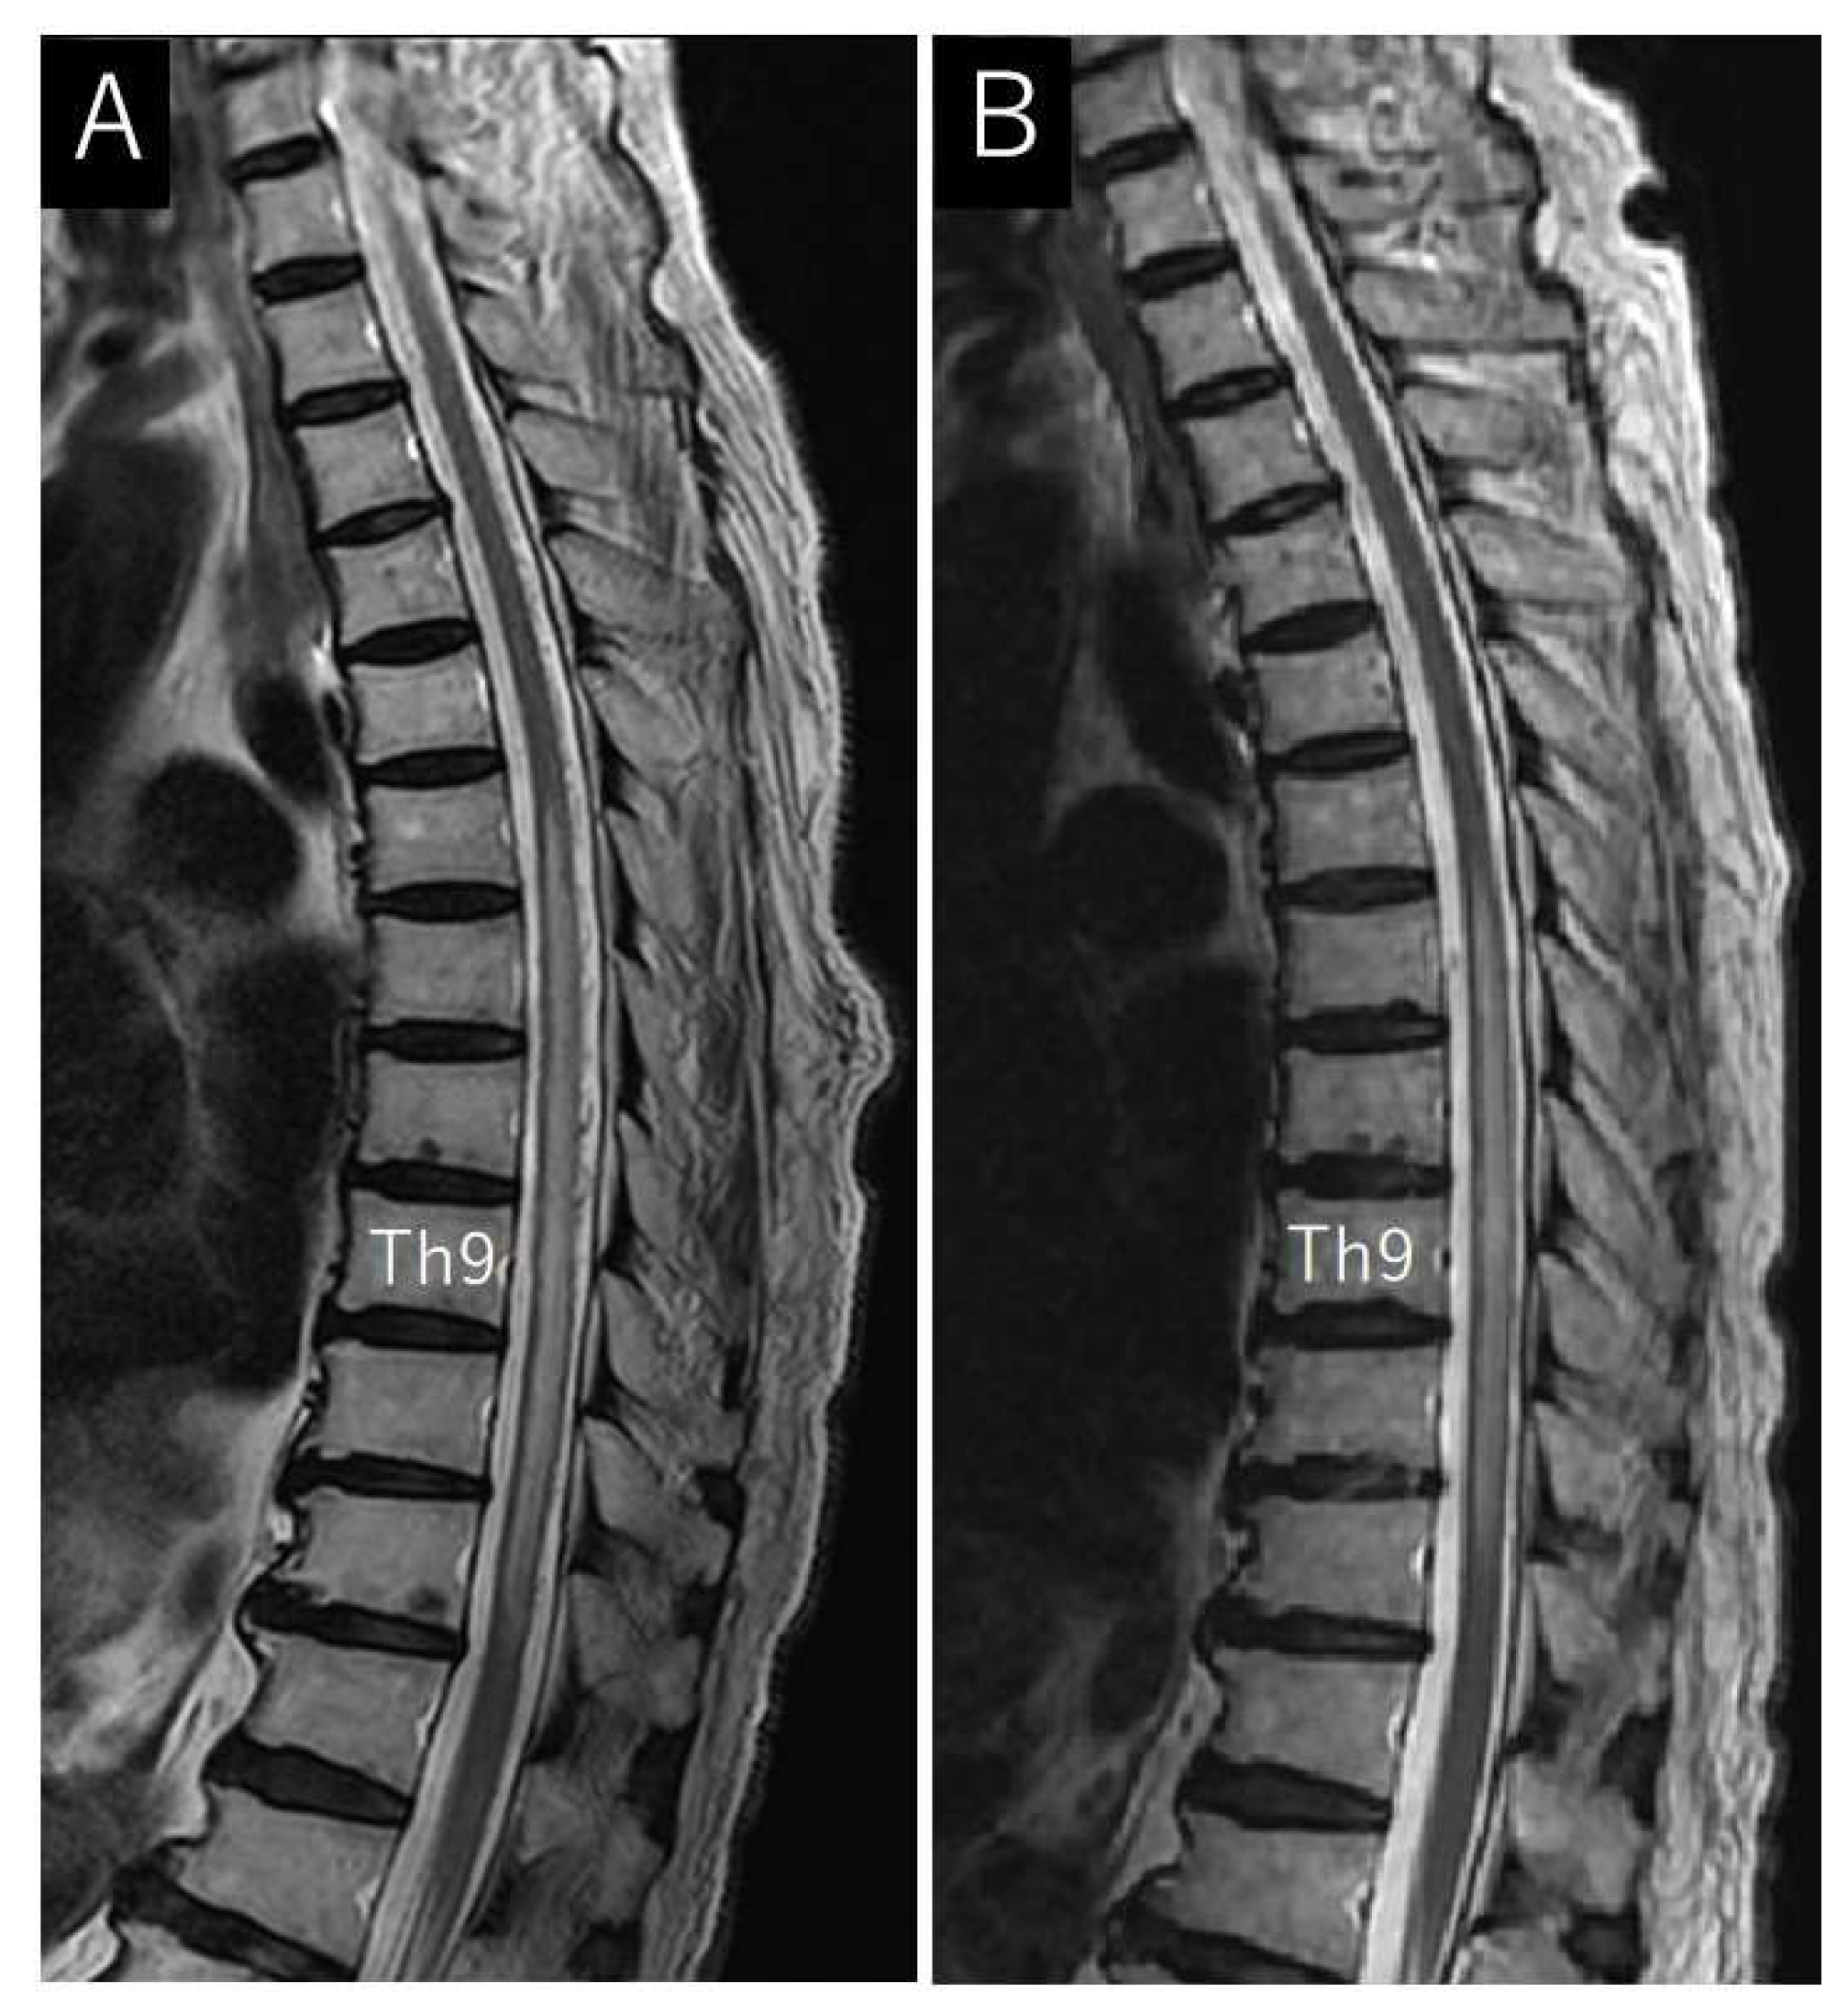

Case Description

4.2. Neuroimaging Findings